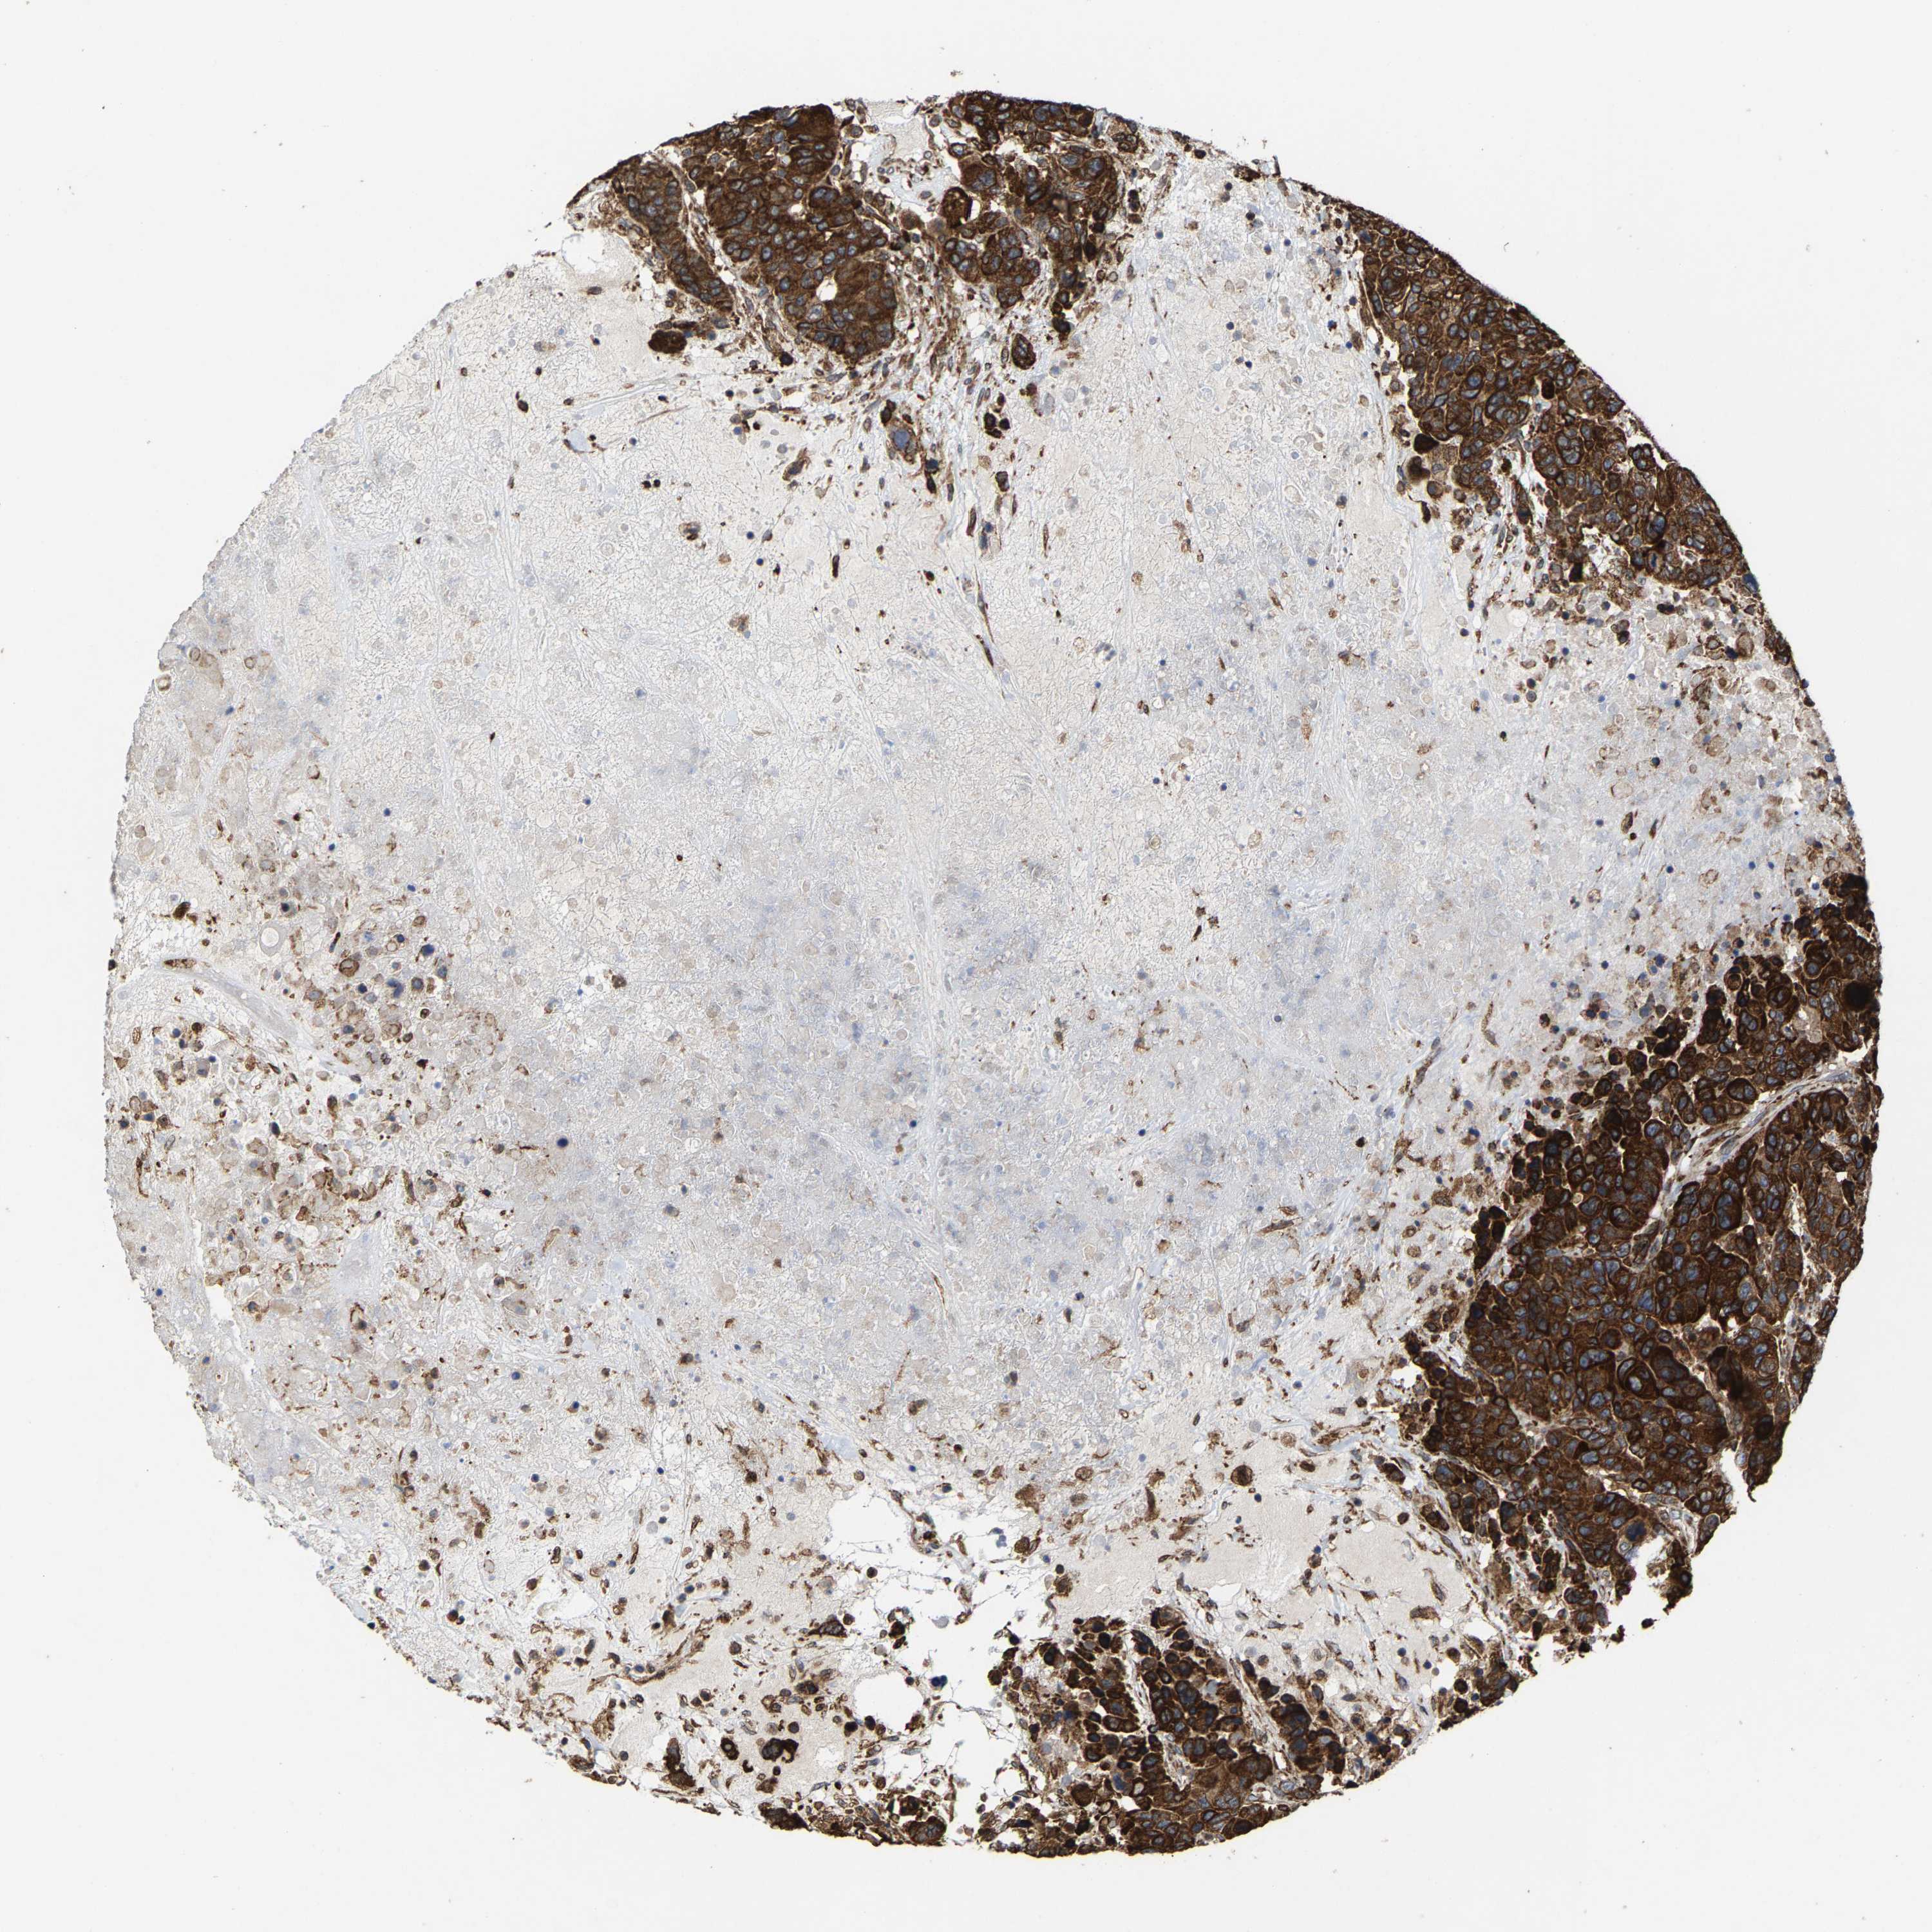

CANCER BREAST CANCER Show tissue menu

BRCA TCGA BRCA VALIDATION PROTEIN EXPRESSION